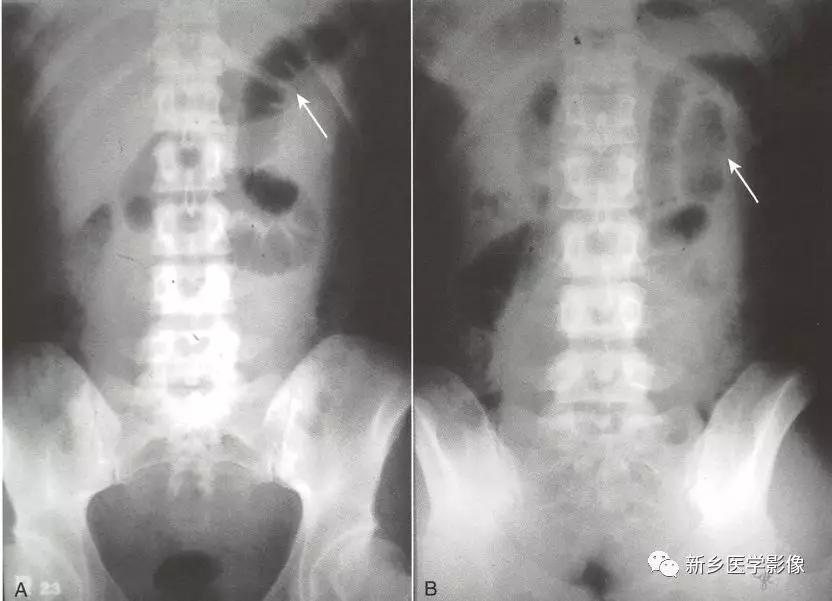

-

在传统X线片,可见一个或两个持续扩张的小肠肠襻。 持续是指多种体位(仰卧、俯卧、直立)或 多个时间点的腹部多次系列检查均提示同一肠襻扩张。

扩张是指小肠肠管直径持续大于2.5cm,功能性肠梗阻小肠扩张程度常常比机械性肠梗阻轻。 大肠作为哨兵襻则较为少见,但一些特殊情况下也可以发生,如阑尾炎时盲肠扩张。

在哨兵襻内通常可见气-液平面。

在局限性肠梗阻中,直肠及乙状结肠往往可见气体影。